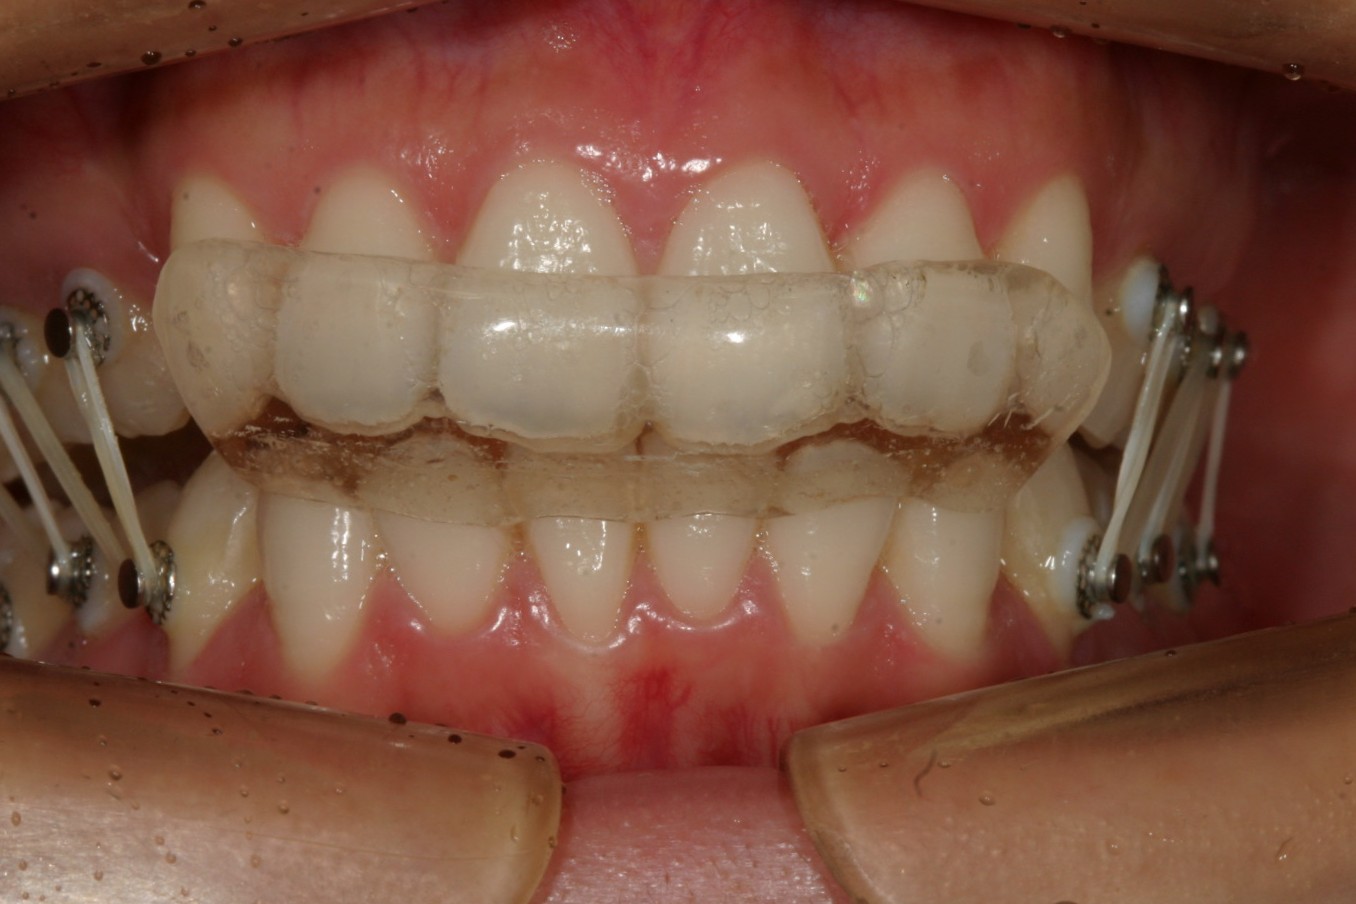

前歯に自家製バイトアップジグが入ってアップダウンエラスティック使用してます。